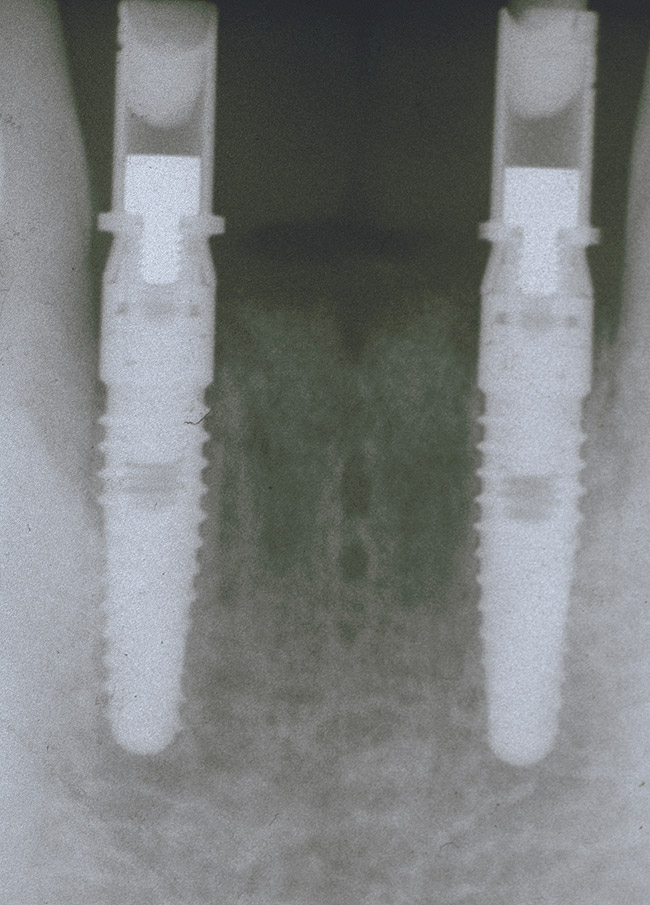

This patient has been followed for 4 years with no complications and no discernable clinical changes in soft or hard tissue levels (Figure 12).

Figure 12  The 4-year postoperative radiograph.

Figure 12